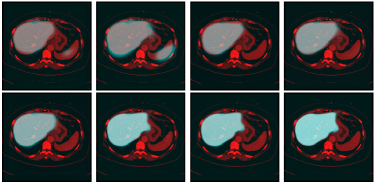

Refer to caption

Figure 6: Illustrations of the role of the likelihood liver map. From the first column to the last, outcomes of graph cut without the likelihood liver map, convolutional neural networks and the proposed integrated model for two typical images are displayed respectively in red. The ground truth is in blue

To better understand the role of the learned liver likelihood map, Fig. 6 depicts the outputs of the graph cut without the liver likelihood map, 3D CNNs and the proposed method for two typical images in red. The ground truth segmentations drawn by experts are in blue. Obviously, incorporated with the liver likelihood map, the proposed model can achieve a better agreement with the ground truth.